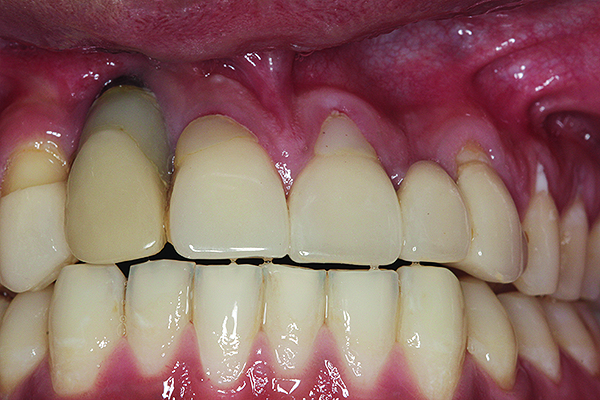

The implant restoration and surrounding soft tissue seen in Fig 3, 5 years following treatment.

Figure 4

Maxillary right lateral incisor implant restoration with severe bone and soft tissue loss is classified a major complication which may not be completely reversible.

Figure 5